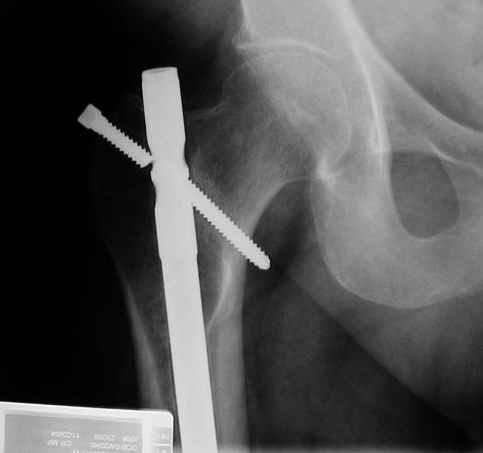

X-ray is of proximal locking screw failure in a 50 male with diaphyseal nonunion.

I would appreciate suggestions for deaaling with this. With the screw broken near the lateral edge it concerns me that trying to pull the nail out might fx the neck. I would like to do an exchange nailing for the diaphyseal nonunion.Thanks for your thoughts.